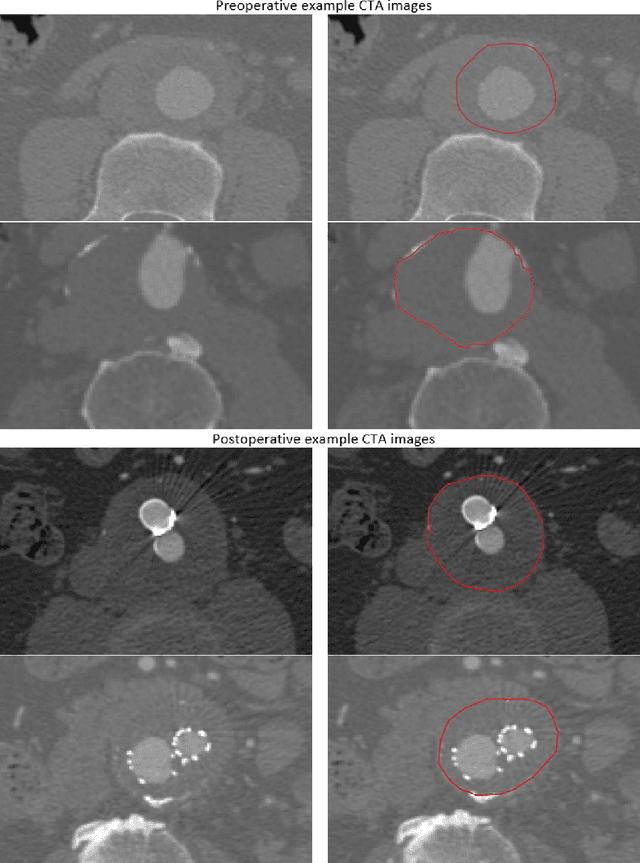

Abstract:An abdominal aortic aneurysm (AAA) is a focal dilation of the aorta that, if not treated, tends to grow and may rupture. A significant unmet need in the assessment of AAA disease, for the diagnosis, prognosis and follow-up, is the determination of rupture risk, which is currently based on the manual measurement of the aneurysm diameter in a selected Computed Tomography Angiography (CTA) scan. However, there is a lack of standardization determining the degree and rate of disease progression, due to the lack of robust, automated aneurysm segmentation tools that allow quantitatively analyzing the AAA. In this work, we aim at proposing the first 3D convolutional neural network for the segmentation of aneurysms both from preoperative and postoperative CTA scans. We extensively validate its performance in terms of diameter measurements, to test its applicability in the clinical practice, as well as regarding the relative volume difference, and Dice and Jaccard scores. The proposed method yields a mean diameter measurement error of 3.3 mm, a relative volume difference of 8.58 %, and Dice and Jaccard scores of 87 % and 77 %, respectively. At a clinical level, an aneurysm enlargement of 10 mm is considered relevant, thus, our method is suitable to automatically determine the AAA diameter and opens up the opportunity for more complex aneurysm analysis.

Abstract:Computerized Tomography Angiography (CTA) based follow-up of Abdominal Aortic Aneurysms (AAA) treated with Endovascular Aneurysm Repair (EVAR) is essential to evaluate the progress of the patient and detect complications. In this context, accurate quantification of post-operative thrombus volume is required. However, a proper evaluation is hindered by the lack of automatic, robust and reproducible thrombus segmentation algorithms. We propose a new fully automatic approach based on Deep Convolutional Neural Networks (DCNN) for robust and reproducible thrombus region of interest detection and subsequent fine thrombus segmentation. The DetecNet detection network is adapted to perform region of interest extraction from a complete CTA and a new segmentation network architecture, based on Fully Convolutional Networks and a Holistically-Nested Edge Detection Network, is presented. These networks are trained, validated and tested in 13 post-operative CTA volumes of different patients using a 4-fold cross-validation approach to provide more robustness to the results. Our pipeline achieves a Dice score of more than 82% for post-operative thrombus segmentation and provides a mean relative volume difference between ground truth and automatic segmentation that lays within the experienced human observer variance without the need of human intervention in most common cases.